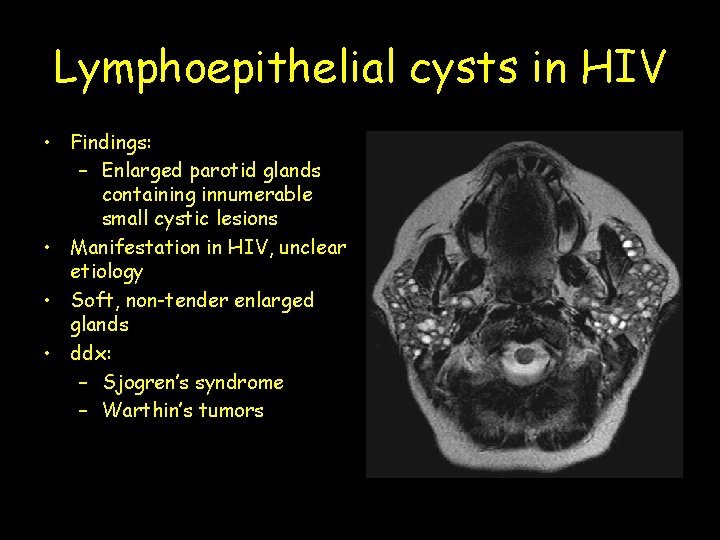

Lymphoepithelial cysts in HIV • Findings: – Enlarged parotid glands containing innumerable small cystic lesions • Manifestation in HIV, unclear etiology • Soft, non-tender enlarged glands • ddx: – Sjogren’s syndrome – Warthin’s tumors